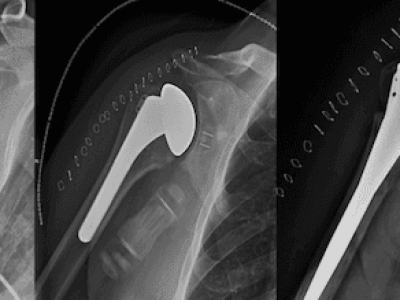

Overview: Stress fractures of the acromion and scapular spine are common complications after reverse total shoulder arthroplasty (RTSA), a type of shoulder replacement surgery. These fractures occur due to the increased stress on the shoulder bones after surgery. What are…

Overview: Proximal humerus fractures are breaks in the upper part of the arm bone near the shoulder. They are common in young people with high-energy injuries and older adults with low-energy falls. What is the Proximal Humerus? The proximal humerus…

Overview: Greater tuberosity fractures are breaks in the upper part of the humerus (arm bone) and often occur due to trauma or repetitive stress, especially in active individuals or athletes. What is the Greater Tuberosity? The greater tuberosity is a…